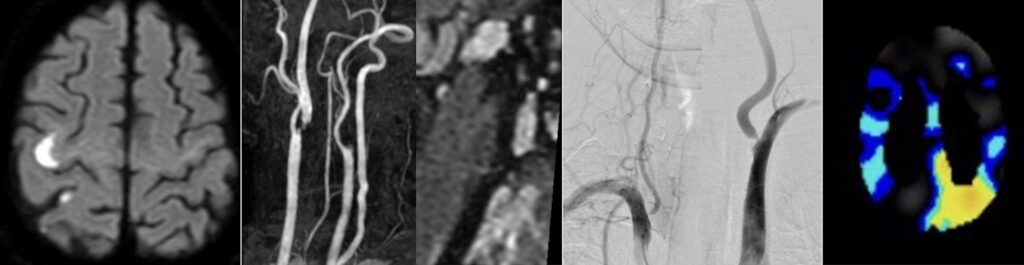

251021火 75歳男性、左内頸動脈閉塞、両側椎骨動脈狭窄を伴う右内頸動脈狭窄症に対してCEAを行いました。 2026 1/23 内頸動脈狭窄 2025年12月11日2026年1月23日多発狭窄で血行力学的脳虚血も合併している脳梗塞発症の右内頸動脈狭窄症に対して血栓内膜剥離術を行いました。術後、無症状ですがSPECT上過還流の所見が出ましたので、1週間以上降圧管理を行い、無事何事もなく退院されました。ScreenshotScreenshotScreenshotScreenshotScreenshotScreenshotScreenshotScreenshot 内頸動脈狭窄 よかったらシェアしてね! URLをコピーしました! URLをコピーしました! 251019日 今週は越前陶芸の里と漁り火温泉に行きました。 251024金 橋本信夫先生に久しぶりにお会いしました。 この記事を書いた人 kikuta 関連記事 血栓内膜剥離術(CEA)を行いました。 2025年2月26日 右内頸動脈狭窄をCEAしました 2025年2月4日 240416火 続いて、84歳の症候性内頸動脈狭窄をCEAを行いました。 2025年1月29日 久しぶりにCEAをやりました 2023年9月27日